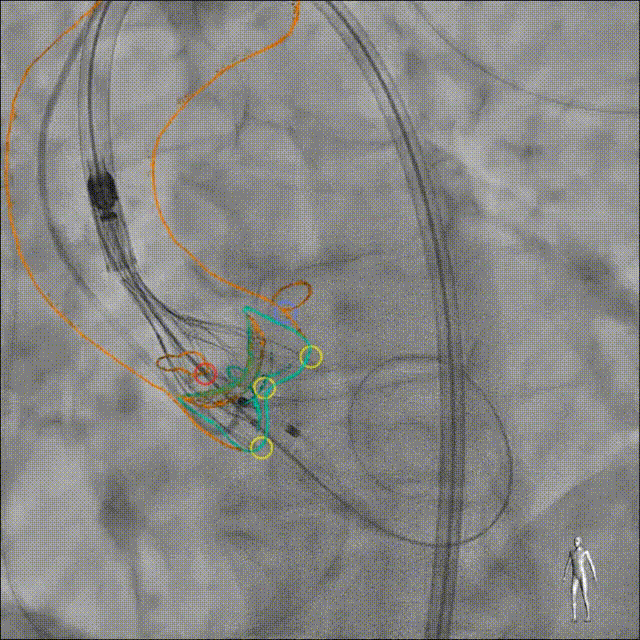

Heart Navigator通过将CT或MRI数据与实时X光透视影像融合,动态呈现手术器械与解剖结构的关系。医生在术中能够实时看到关键部位的分布和标记点,确保手术路径的安全性和准确性。这种实时导航技术还支持术中影像的自由调整,使医生可以快速响应突发情况。

TAVI:主动脉瓣与实时透视融合

LAAO:左心耳与透视实时融合

Heart Navigator在临床中的表现尤为突出。例如,在一例TAVI手术中,一名75岁的患者因主动脉瓣狭窄接受治疗。Heart Navigator通过术前的CT影像分割,精准地提供了植入瓣膜的最佳角度建议。术中,实时导航功能进一步确保了手术的顺利进行,成功避免了冠状动脉的阻塞。

病例1:经股入路TAVI手术